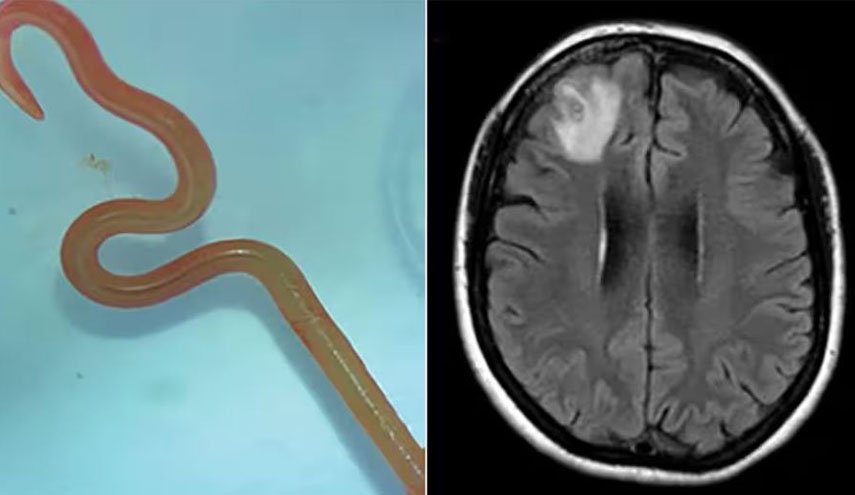

دودة الدماغ.. علامات خطر لا ينبغي تجاهلها

جراحة الأعصاب بيتسي غرونش أوضحت بعض أسباب هذا الداء وأعراضه لموقع "بز فييد" حيث قالت إن "ديدان الدماغ" هي طفيليات تصيب أجزاء من أجسامن.

وأضافت: "الأكثر شيوعًا دودة شريط لحم الخنزير، تينيا سوليوم (أو داء الكيسات العصبية)".

بحسب بيتسي فإن هذه الدودة لا يمكنها الانتقال إلى الدماغ لكن يرقاتها يمكنها ذلك، حيث تضع الدودة يرقاتها بمجرد دخولها للأمعاء مستخدمة أجسامنا كوسيط، وإذا لم يتم طرد البيض من أجسامنا من خلال البراز، فقد تنمو إلى يرقات.

وتابعت: "قد يستغرق ظهور أعراض عدوى الدماغ شهورا إلى سنوات، حيث لا تظهر الأعراض عادة إلا بعد موت اليرقات، وعندما تظهر في الدماغ، تشمل الأعراض الغثيان والنوبات والصداع".